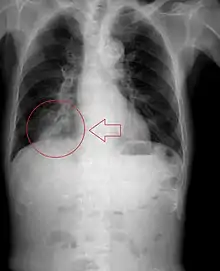

Pulmonary aspiration

Pulmonary aspiration is the entry of material such as pharyngeal secretions, food or drink, or stomach contents from the oropharynx or gastrointestinal tract, into the larynx (voice box) and lower respiratory tract, the portions of the respiratory system from the trachea (windpipe) to the lungs. A person may inhale the material, or it may be delivered into the tracheobronchial tree during positive pressure ventilation. When pulmonary aspiration occurs during eating and drinking, the aspirated material is often colloquially referred to as "going down the wrong pipe".

In healthy people, aspiration of small quantities of material is common and rarely results in disease or injury. People with significant underlying disease or injury are at greater risk for developing respiratory complications following pulmonary aspiration, especially hospitalized patients, because of certain factors such as depressed level of consciousness and impaired airway defenses (gag reflex and respiratory tract antimicrobial defense system). The lumen of the right main bronchus is more vertical and slightly wider than that of the left, so aspirated material is more likely to end up in this bronchus or one of its subsequent bifurcations.